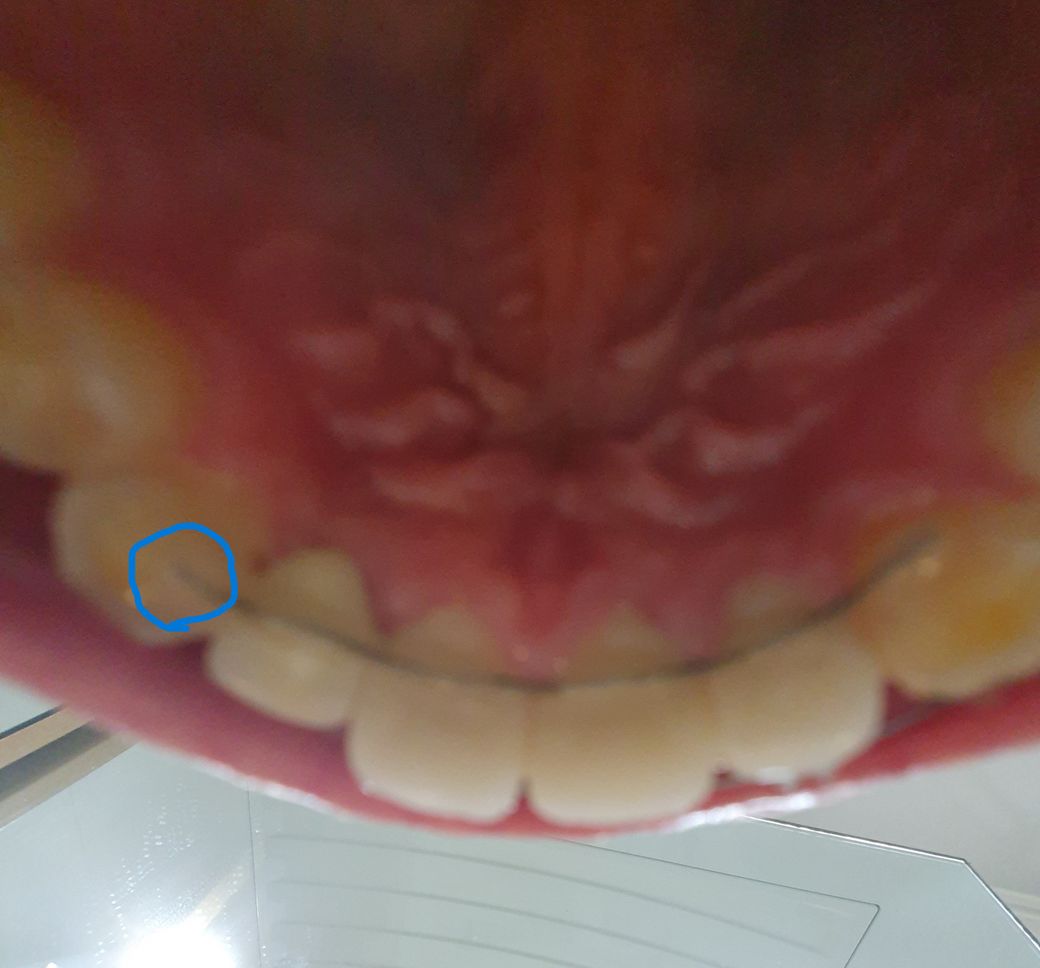

교정끝나고 고정유지장치를 붙였는데 아랫니랑 많이 닿아요 재조정 혹은 재제작 가능한가요?

얼마전 앞니 부분 교정을 끝내고 뒤쪽에 고정 유지장치를 부착했습니다. 치위생사분이 해주시더라구요.

유지장치가 딱봐도 1자가 아닌 약간 사선으로 부착이 되어있더라구요. 앞니 4개는 보철물입니다..ㅠ

가만히 딱딱거렸을때와 좌우치아 갈때는 닿지않지만 음식물 저작 할때는 왼쪽 아랫니랑 심하게 닿습니다 왼쪽에서 오른쪽 45도로 안으로 갈때입니다. 많이 닿아요. 고정철사 높이 만큼 닿습니다.

원래 저렇게 잇몸 바로 닿을듯 말듯 치간칠솔도 들어가지않는 위치에 붙히나요? 아랫니랑 부딪히지 않을려고 붙힌건 압니다만...

• 1번 째 사진